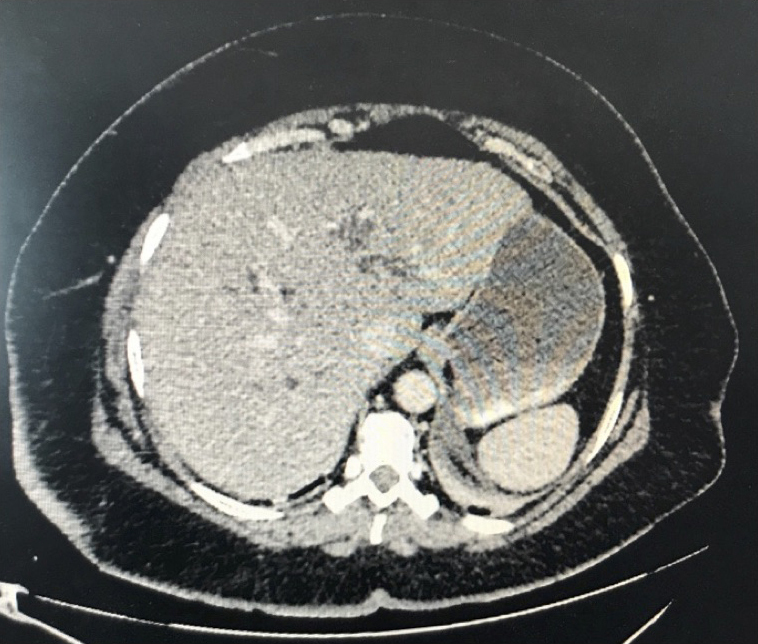

La douleur de la pancréatite est épigastrique irradiant dans le dos, majorée par la respiration profonde et la position antalgique est en chien de fusil.